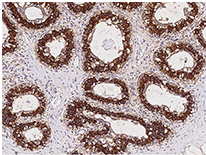

Anti-FASN Ab, Rabbit pAb: (Cat#: 100685-T10)

Immunochemical staining of human FASN in the human breast. Image Credit: Sino Biological Inc.

- Applications: IHC-P, ICC/IF